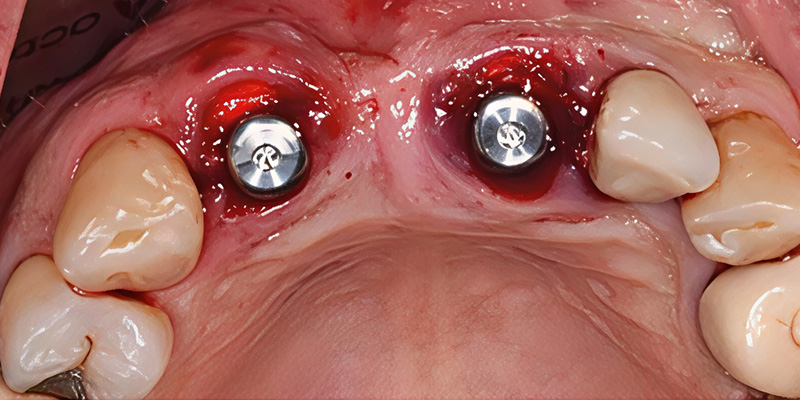

Deux implants CAMLOG® PROGRESSIVE-LINE de 3,8 mm × 13 mm ont été posés dans les alvéoles d’extraction.

Fig. 4 : Mise en place de l’implant.

Une greffe osseuse simultanée a été réalisée en utilisant MinerOss® XP dans l’alvéole 21 afin de favoriser un volume osseux accru et la stabilité. Une membrane de collagène résorbable Striate+™ a été insérée en vestibulaire entre le MinerOss® XP et la gencive.

Fig. 5 : Membrane placée pour stabiliser le matériau de greffe osseuse autour de l’implant.